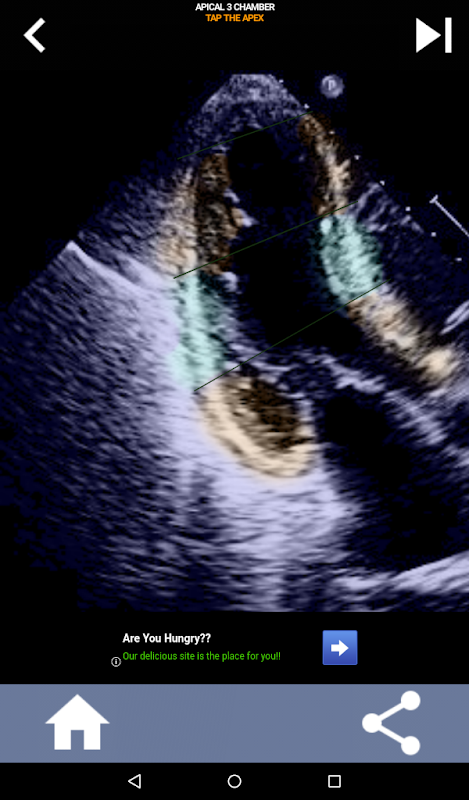

Pendekatan visual berasaskan kuiz untuk mempelajari segmen jantung AHA: Ekokardiografi

Aplikasi ini akan menguji pengetahuan anda menggunakan imej gema sebenar, yang sering saya dapati sebagai kaedah pengajaran terbaik.